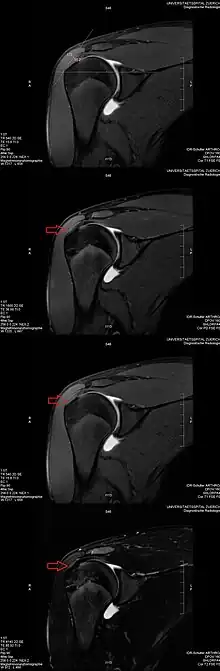

O artefato do ângulo mágico refere-se ao aumento do sinal em sequências com tempo de eco (TE) curto (por exemplo, T1 ou sequências de eco de giro PD) em imagens de RM vistas em tecidos com fibras de colágeno bem ordenadas em uma direção (por exemplo, tendão ou cartilagem hialina articular).[4] Este artefato ocorre quando o ângulo que tais fibras fazem com o campo magnético é igual a θm.

Exemplo: Este artefato entra em jogo quando se avaliam os tendões do manguito rotador do ombro. O efeito do ângulo mágico pode criar uma aparência de tendinite supraespinhal.